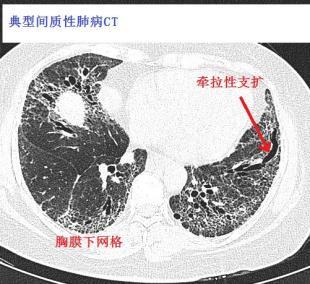

间质性肺炎影像学,间质性肺炎肺纤维化

网格 ≈ 间质性肺炎 间质性肺炎的影像学表现,复杂的很复杂,有时候和

间质性肺炎ct

间质性肺炎ct表现

间质性肺炎ct图片

间质性肺炎ct图片特点